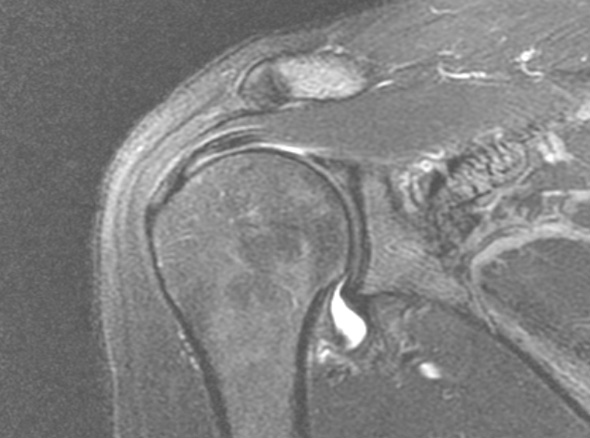

오십견은 어깨를 감싸고 있는 관절 조직인 관절낭에 염증이 발생하면서

유착되어 어깨의 움직임이 제한되고 통증이 유발되는 질환입니다.

즉각적으로 통증을 완화해주고 어깨의 가동범위를 개선해주는 시술입니다.

주사 치료, 도수 치료 등을 하였으나 증상이 지속되는 경우

극심한 통증으로 스트레칭이 불가한 경우

정상 상태로 회복되는 걸리는 시간과 통증을 최소화 하고 싶은 경우